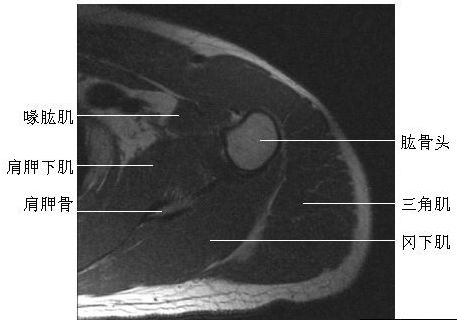

肩关节横断面(一)